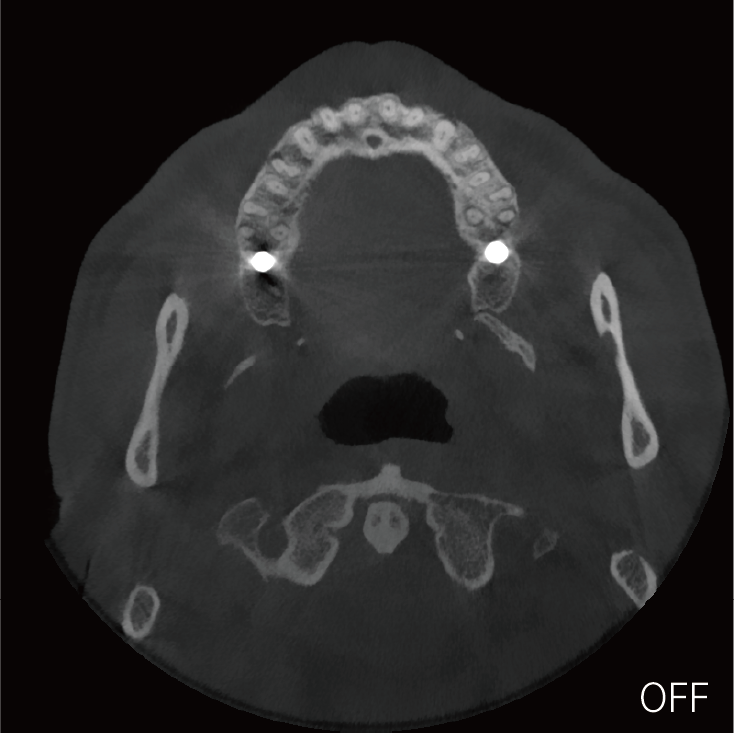

超能去伪 至臻影像

临床样片